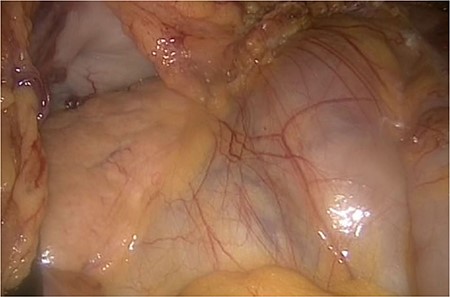

We accidentally opened the dorsal peritoneum (Fig. 2), and found the small bowel underneath - retroperitoneal (Fig. 3).